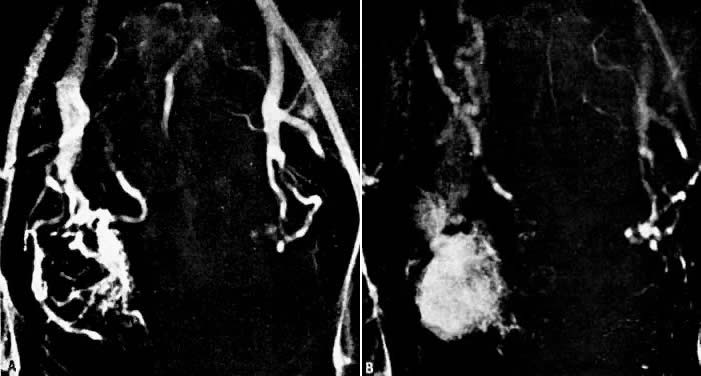

Case 5.

In this 36-year-old patient, bleeding occurred after successful chemotherapy for gestational trophoblastic disease (hydatidiform mole). Transfusion was required on two occasions. Figure 22A shows selective left uterine artery injection, demonstrating the uterine artery with supply of a hypervascular fundal mass with early venous drainage. The right uterine artery was normal. The left uterine artery was embolized with polyvinyl alcohol foam particles (300 to 500 μm). This intervention produced complete occlusion of the left uterine artery. A pelvic arteriogram (Fig. 22B) shows occlusion of the left uterine artery and no evidence of a hypervascular mass.

Fig. 22. Case 5. Vascular malformation after successful treatment for hydatidiform mole. A. Left uterine arteriogram showing uterine artery ( curved arrow) with supply of a hypervascular fundal mass ( asterisk) with early venous drainage ( arrow ). B. Pelvic arteriogram after embolization, resulting in occlusion of the left uterine artery ( arrow ).(Vogelzang RL, Nemcek AA, Skirtic Z et al: Uterine arteriovenous malformations: Primary treatment with therapeutic embolization. J Vasc Interv Radiol 2:517, 1991)